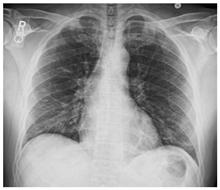

Стандартная РГ имеет низкую чувствительность в выявлении начальных изменений в первые дни заболевания и не может применяться для ранней диагностики. Информативность РГ повышается с увеличением длительности течения пневмонии. Рентгенография с использованием передвижных (палатных) аппаратов является основным методом лучевой диагностики патологии ОГК в отделениях реанимации и интенсивной терапии (ОРИТ). Применение передвижного (палатного) аппарата оправдано и для проведения обычных РГ исследований в рентгеновском кабинете. В стационарных условиях относительным преимуществом РГ в сравнении с КТ являются большая пропускная способность. Метод позволяет уверенно выявлять тяжелые формы пневмоний и отек легких различной природы, которые требуют госпитализации, в том числе направления в ОРИТ.

4. Все выявляемые при лучевых исследованиях признаки, включая КТ-симптомы, не являются специфичными для какого-либо вида инфекции и не позволяют установить этиологический диагноз. Вне клинической (эпидемической) ситуации они не позволяют отнести выявленные изменения к пневмонии COVID-19 и дифференцировать их с другими пневмониями и невоспалительными заболеваниями. Данные лучевого исследования не заменяют результаты обследования на РНК SARS-CoV-2. Отсутствие изменений при КТ не исключают наличие COVID-19 и возможность развития пневмонии после проведения исследования.